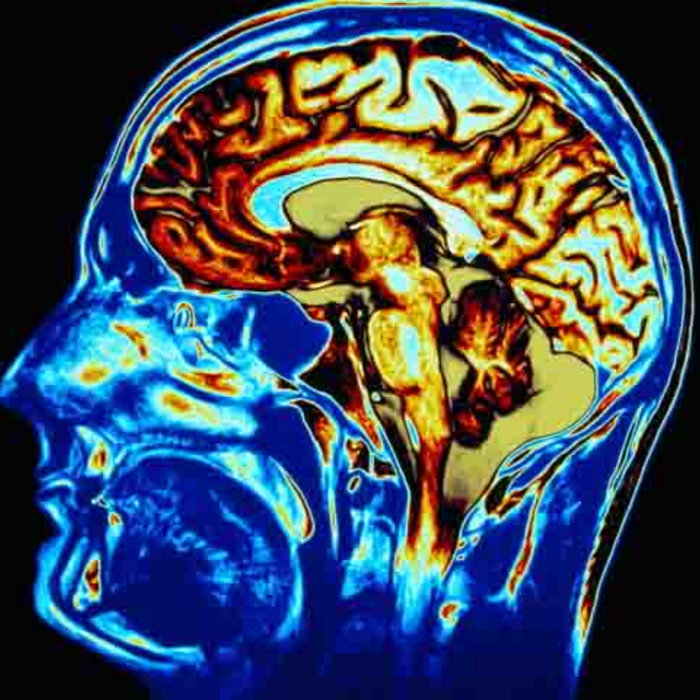

from neurosciencenews.com

What Happens in the Brain When People Make Music Together